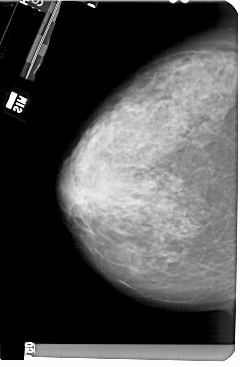

A_1504_1.RIGHT_CC

RIGHT_CC LINES 5491 PIXELS_PER_LINE 3376 BITS_PER_PIXEL 12 RESOLUTION 43.5 OVERLAY